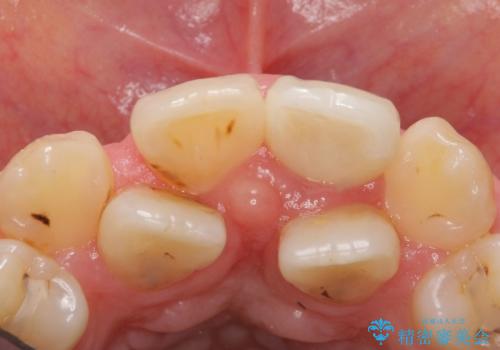

根管治療後、セラミッククラウンによる補綴を行いました。

比較的短い治療期間と自然な仕上がりにご満足頂けました。

ジルコニアクラウン スタンダード